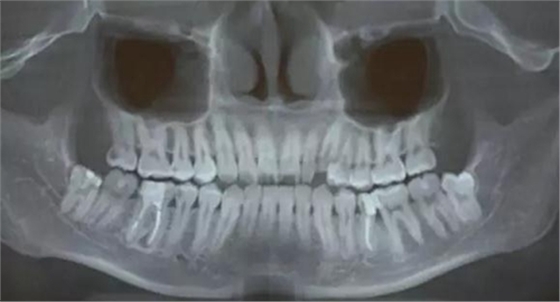

圖3.術(shù)前CBCT全景片重建影像檢查:48牙根與下頜管重疊